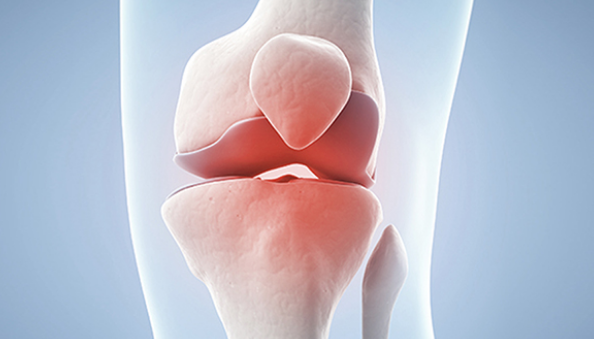

글루코사민은 우리 몸의 연골을 이루는 필수성분으로 관절에 탄력성을 주고, 관절 강도를 높이는 역할을 합니다.

연골의 필수 성분인 글루코사민은 우리 몸에서 원래 스스로 생성되는 성분입니다. 그러나 나이가 들어 가면서 글루코사민 생성 능력은 현저히 감소하게 됩니다. 이에 따라 자연스럽게 관절연골의 완충 능력은 나빠지게 되고, 손상받기 쉬운 상태가 되어 버립니다. 그리고 이 손상이 염증을 유발합니다. 이것이 바로 관절염입니다.

줄어든 글루코사민 생성능력만큼 음식이나 영양제를 통해 글루코사민을 충분히 공급해주면면 연골의 파괴를 막을 수 있고, 연골 세포의 증식을 촉진시킬 수 있습니다. 그러므로, 적절한 글로코사민 섭취는 관절염 등 관절 질환을 앓고 있는 사람들에게 큰 도움을 줄 수 있습니다.